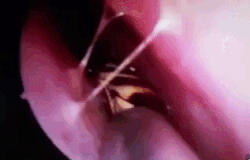

Bác sĩ dùng dụng cụ gắp con gián qua đường mũi của người phụ nữ. Con gián ở trong đây 12 tiếng và sau khi thoát ra ngoài, nó vẫn sống khỏe